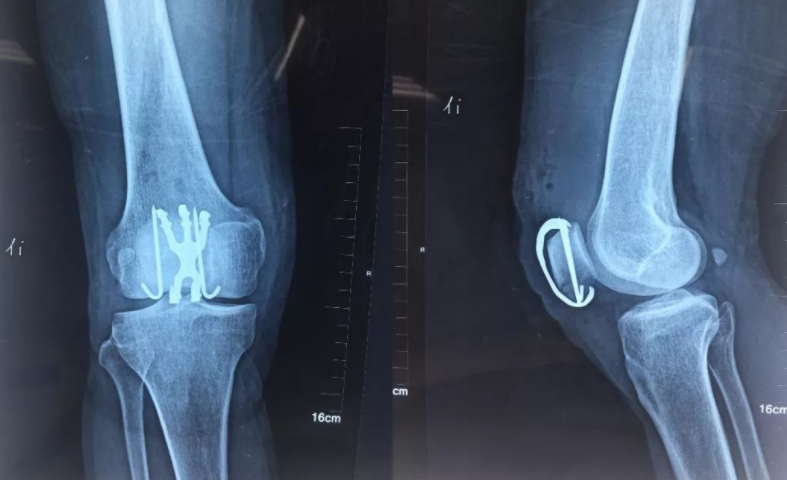

老王今年66岁 , 家住河南安阳 , 本该退休在家 , 安度晚年 , 可现在却因患了骨质疏松 , 摔倒后双腿骨折 , 躺在病床上动弹不得 。

到了病房 , 老王双腿都被打上了石膏 , 医生告诉老王他已经是骨质疏松中晚期了 , 骨骼十分脆弱 。 老王不敢相信 , 他平时生活习惯十分健康 , 不熬夜也不抽烟喝酒 , 怎么会患上骨质疏松?经过医生的了解 , 发现是咸菜害了老王 。